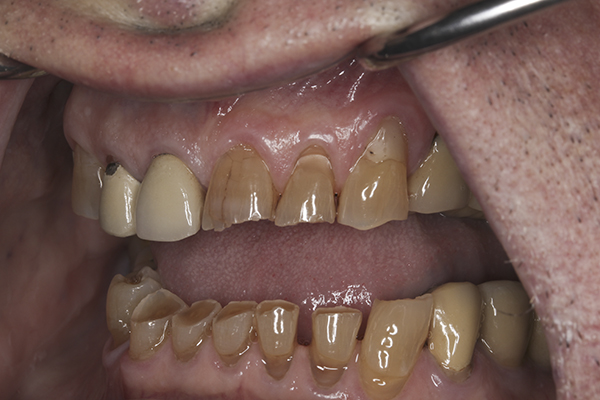

(6.) Preoperative right lateral, open view.

Figure 6

(7.) Preoperative anterior, open view. Note the significant amount of wear, erosion, and abfraction lesions.

Figure 7

(9.) Preoperative right lateral, closed view.

Figure 9

(10.) Preoperative anterior, closed view. Note the end-to-end occlusion of the anterior teeth and the wear on the incisors and centrals resulting in no anterior or canine guidance.

Figure 10